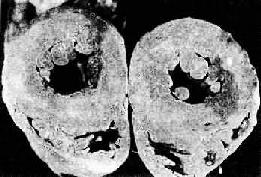

图8-12 高血压病之肾 肾小球入球小动脉管壁玻璃样变性,肾小球纤维化,玻璃样变 临床上,可多年不出现肾功能障碍。晚期由于病变的肾单位越来越多,肾血流量逐渐减少,肾小球滤过率逐渐降低。患者可发生水肿、出现蛋白尿及管型。严重者可出现尿毒症的临床表现。 4.脑的病变 高血压时,由于脑内细动脉的痉挛和病变,患者可出现不同程度的高血压脑病(hypertensive encephalopathy)症状,如头痛、头晕、眼花等,甚至出现高血压危象。患者有明显的中枢神经症状,如意识模糊、剧烈头痛、恶心、呕吐、视力障碍及癫痫发作等。 (1)脑动脉病变:严重的病例细动脉和小动脉管壁可发生纤维素样坏死,可并发血栓形成及微动脉瘤(microaneurysm)。后者好发于壳核、丘脑、脑桥、小脑和大脑,这些部位也是高血压性脑出血及脑梗死发生率最高之处。 (2)脑软化:由于细动脉、小动脉病变造成其所供养区域脑组织缺血的结果,脑组织内可出现多数小软化灶,即微梗死灶(microinfarct)。镜检下,梗死灶内脑组织坏死液化,形成染色较浅、质地疏松的筛网状病灶。灶内可见坏死的细胞碎屑,周围有胶质细胞增生及少量炎性细胞浸润。最后,坏死组织被吸收,由胶质瘢痕修复。由于软化灶较小,一般不引起严重后果。 (3)脑出血:是高血压最严重的且往往是致命性的并发症。多为大出血灶,常发生于基底节、内囊,其次为大脑白质、脑桥和小脑。出血区域的脑组织完全被破坏,形成囊腔状,其内充满坏死的脑组织和凝血块。有时出血范围甚大,可破入侧脑室(图8-13)。引起脑出血的原因一方面由于细、小动脉的病变,另一方面,脑出血多发生于基底节区域(尤以豆状核最多见),供养该区的豆纹动脉从大脑中动脉呈直角分出,直接受到大脑中动脉压力较高的血流冲击,易使已有病变的豆纹动脉破裂出血。此外,血压突然升高(如情绪激动时)亦易使病变的动脉破裂出血。临床上,患者常骤然发生昏迷、呼吸加深和脉搏加快。严重者可发生陈-施(Cheyne-Stokes)呼吸、瞳孔反射及角膜反射消失、肢体弛缓、肌腱反射消失、大小便失禁等症状。出血灶扩展至内囊时,引起对侧肢体偏瘫及感觉消失。出血灶破入侧脑室时,患者发生昏迷,常导致死亡。左侧脑出血常引起失语,脑桥出血可引起同侧面神经麻痹及对侧上下肢瘫痪。

图8-13 高血压病之脑出血 大脑左侧内囊出血并破入侧脑室 5.视网膜的病变 视网膜中央动脉亦常发生硬化。眼底镜检查可见这些血管迂曲,颜色苍白,反光增强,呈银丝样改变。动、静脉交叉处静脉呈受压现象。严重者视乳头发生水肿,视网膜渗出和出血,患者视物模糊。 (二)恶性高血压 恶性高血压(malignant hypertension)又称为急进型高血压,可由良性高血压恶化而来,或起病即为急进性。病理变化主要见于肾和脑。 1.肾的变化 镜检下,可见细动脉坏死(arteriolonecrosis)(纤维素样坏死),坏死累及内膜和中膜,并有血浆成分内渗(insudation),使管壁极度增厚。HE染色切片上,受累血管壁呈嗜伊红性和折光性,免疫组织化学检查证明其中含有纤维蛋白、免疫球蛋白、补体。可见核碎片,但炎性细胞浸润极少见。有时可见到坏死性细动脉炎,在坏死的血管壁及周围有单核细胞及中性粒细胞浸润,但这种动脉炎不累及弓形动脉及叶间动脉。入球动脉坏死常波及肾小球,使肾小球毛细血管丛发生节段性坏死。细动脉坏死常并发血栓形成,可引起出血及微梗死。小动脉的变化颇具特征性,表现为增生性动脉内膜炎(proliferative endarteritis),内膜显著增厚,其内有多数SMC增生,并呈向心性排列,形成层状葱皮样病变。SMC产生大量胶原及蛋白多糖,管腔陷于高度狭窄。然而,这些变化并非恶性高血压所特有,类似的变化亦见于肾移植慢性排斥反应、进行性系统性硬化等。肉眼观,肾表面平滑,可见多数出血点,切面可见多数斑点状微梗死灶。 2.脑的变化 脑的细、小动脉亦可发生同样病变,常引起局部缺血、微梗死和脑出血。 临床上,有严重的高血压,血压值超过30.66/17.3kPa(230/130mmHg)。可发生高血压脑病。常有持续蛋白尿、血尿及管型尿。患者多于一年内因尿毒症、脑出血或心力衰竭致死。